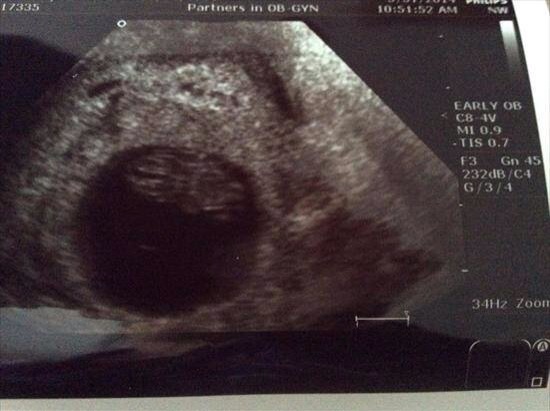

8 weeks.

Transvaginal

Asked which side, tech said she thinks rightAttachment 18163